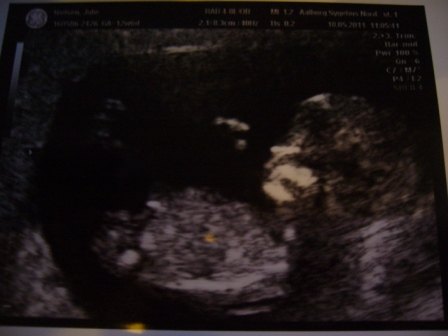

Så var vi til NF scanning idag, og vores lille baby har det bare godt i maven. Den er helt fin, og nakkefolden var 1:11111 - så der er vidst ikke noget at bekymre sig for der

Se lige den lille - den vinker jo nærmest ud til os

Vedhæftede fotos (klik for at se i fuld størrelse)